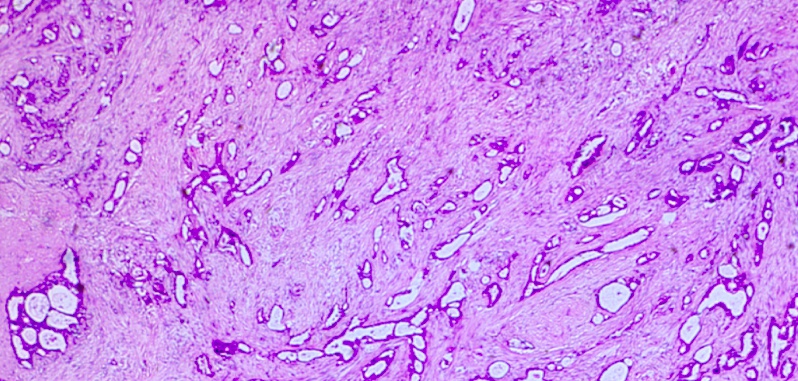

Invasive Ductal Carcinoma

_is the most common type of invasive carcinoma in the breast (>80% of cases), and will classically form duct-like structures., Round ducts

_Biopsy shows duct-like structures in a desmoplastic stroma. The gross appearance reveals a gray-white tumor with stellate morphology, and reactive fibroplasia (desmoplasia) leads to a gritty induration.

.,